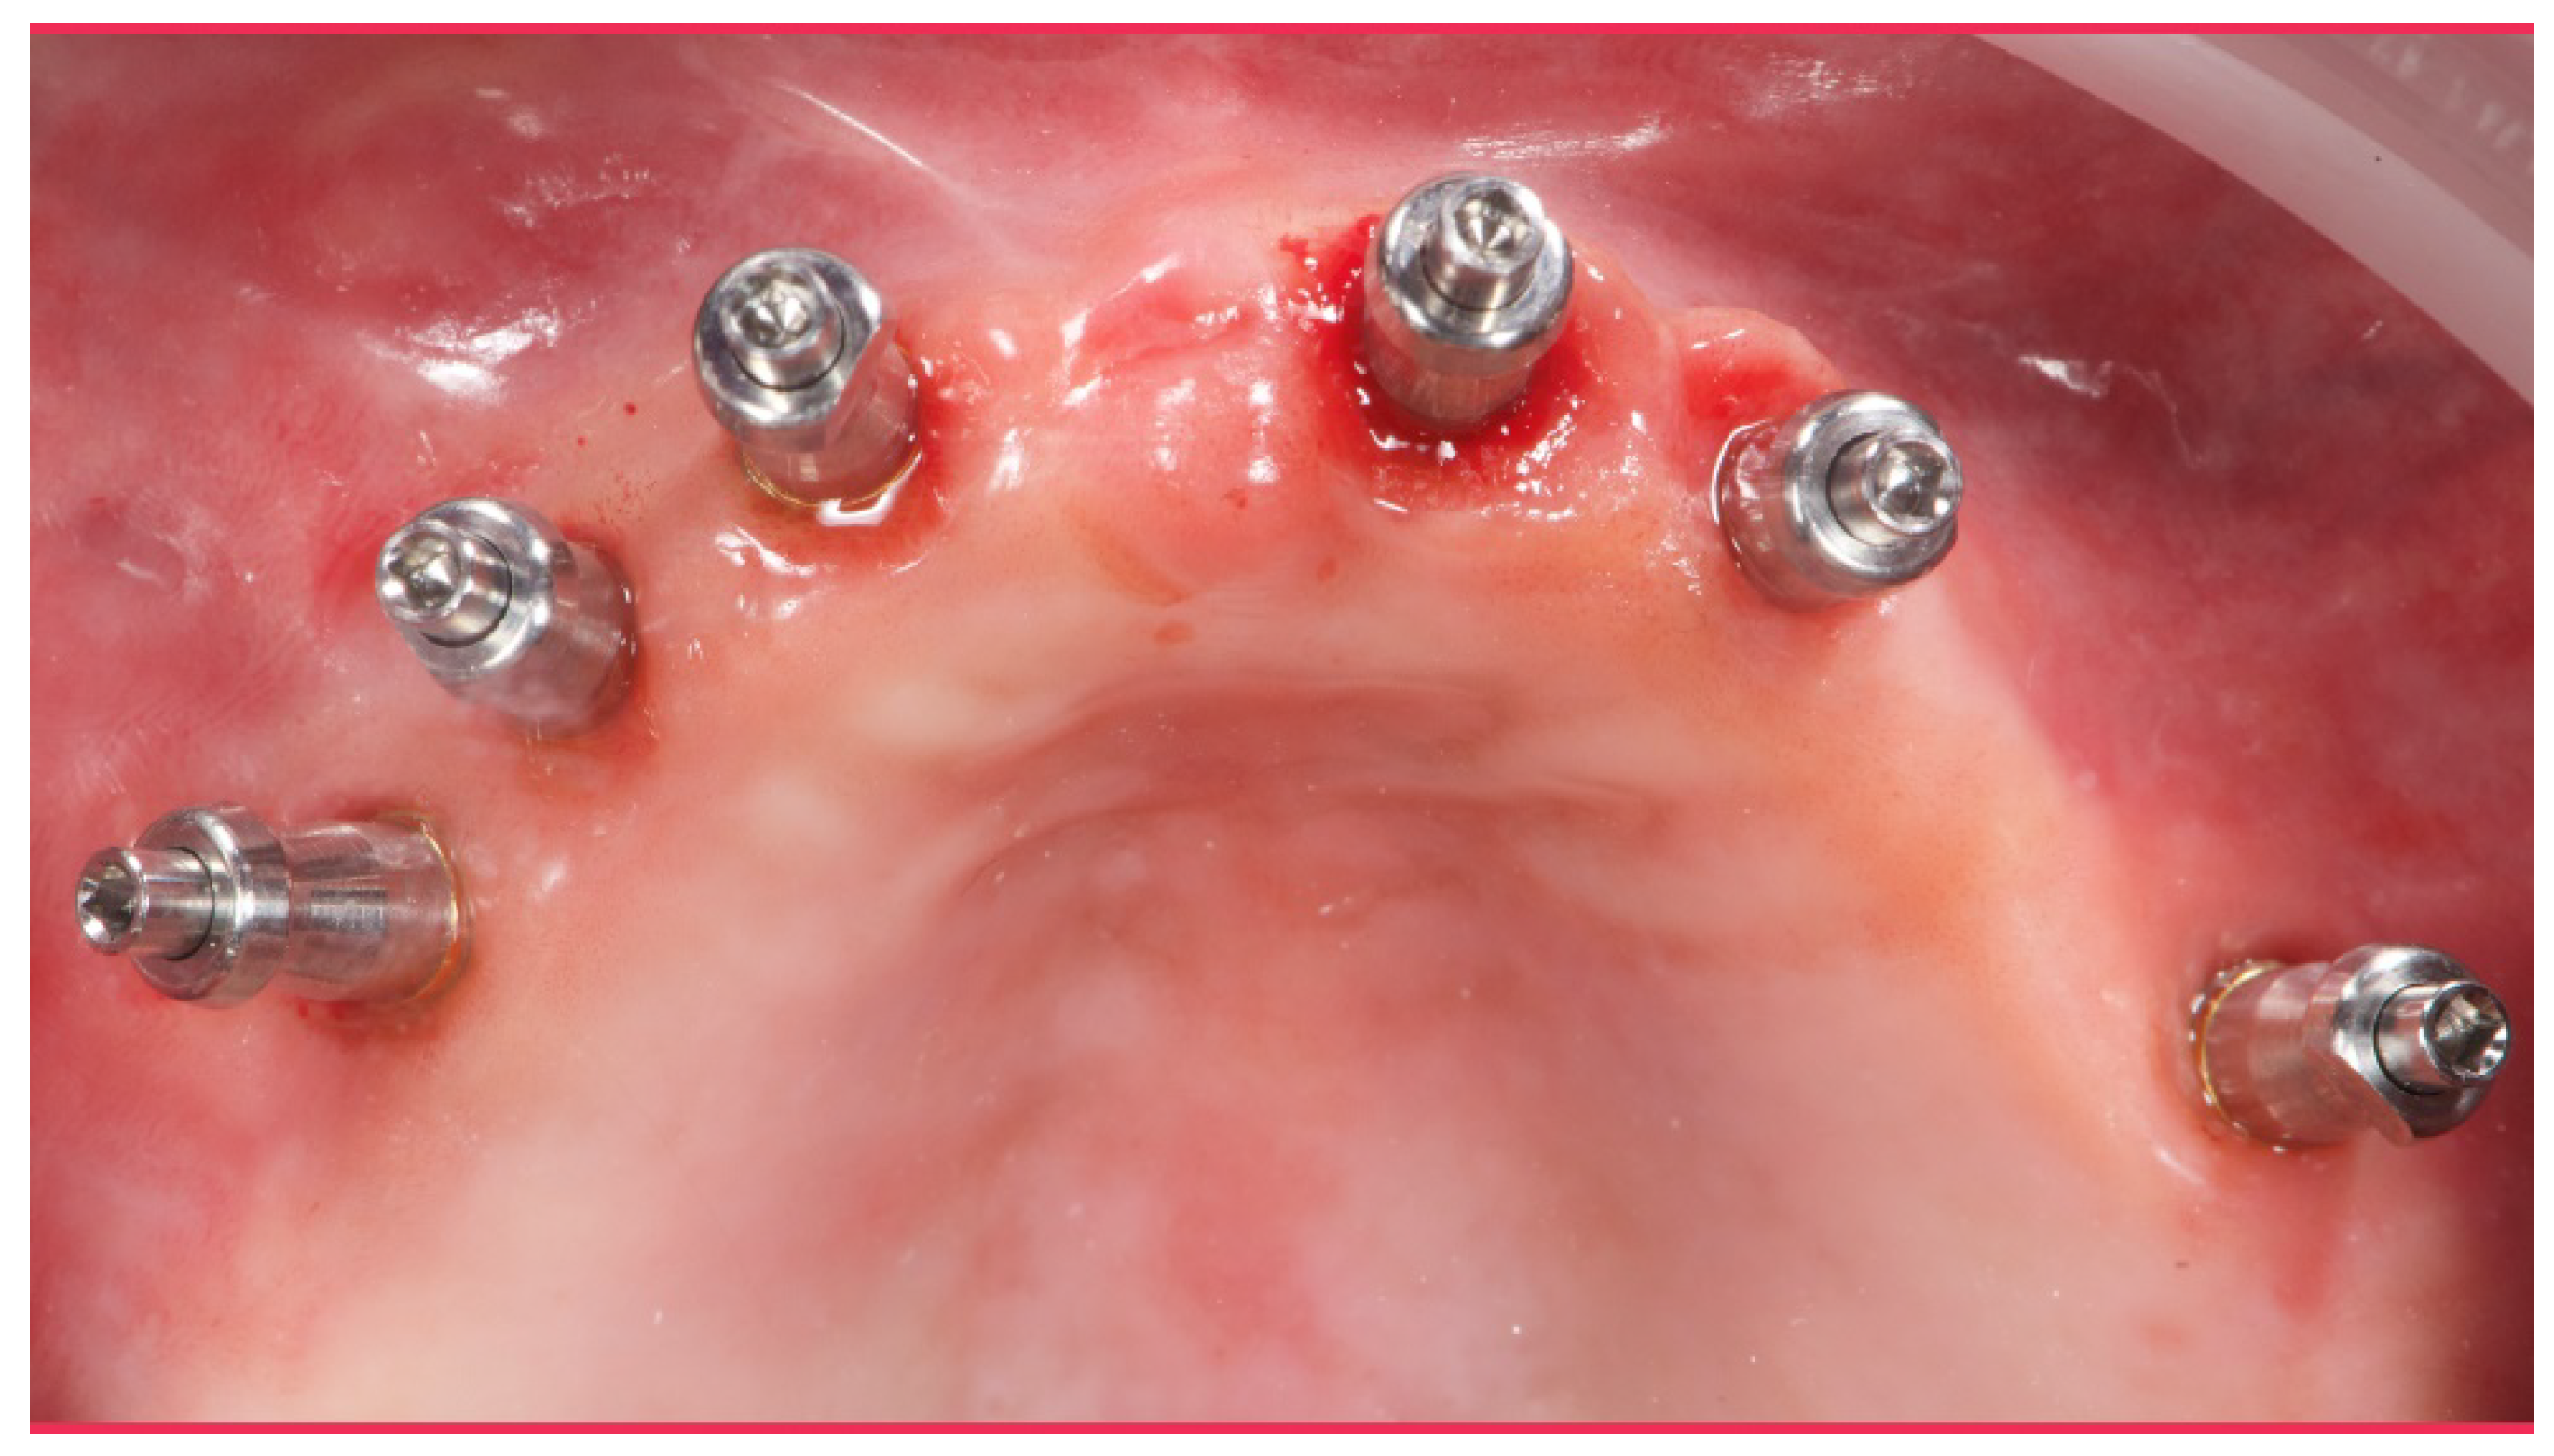

Figure 8.

Analogical transfer screwed on OT Equator for classic impression technique.